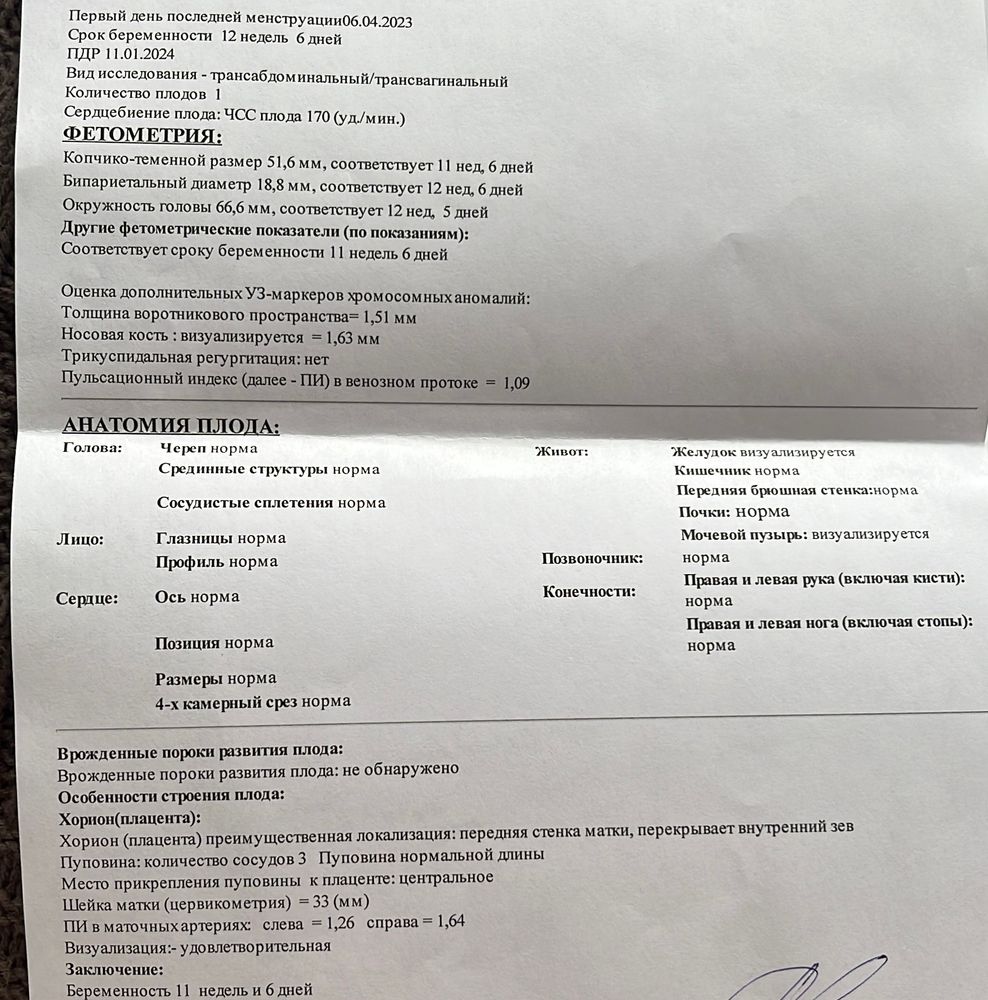

Скрининг 11,6 🎈☺️

Ну что, прошли мы первый скрининг) 40 минут не хотела моя козявка перевернуться как надо😤и то носик не могли и воротник измерить как надо) , смущает шейка в 33 мм и перекрытие внутреннего зева☹️Ре молчит пока, а так все замечательно 😀 ждем кровь🫠